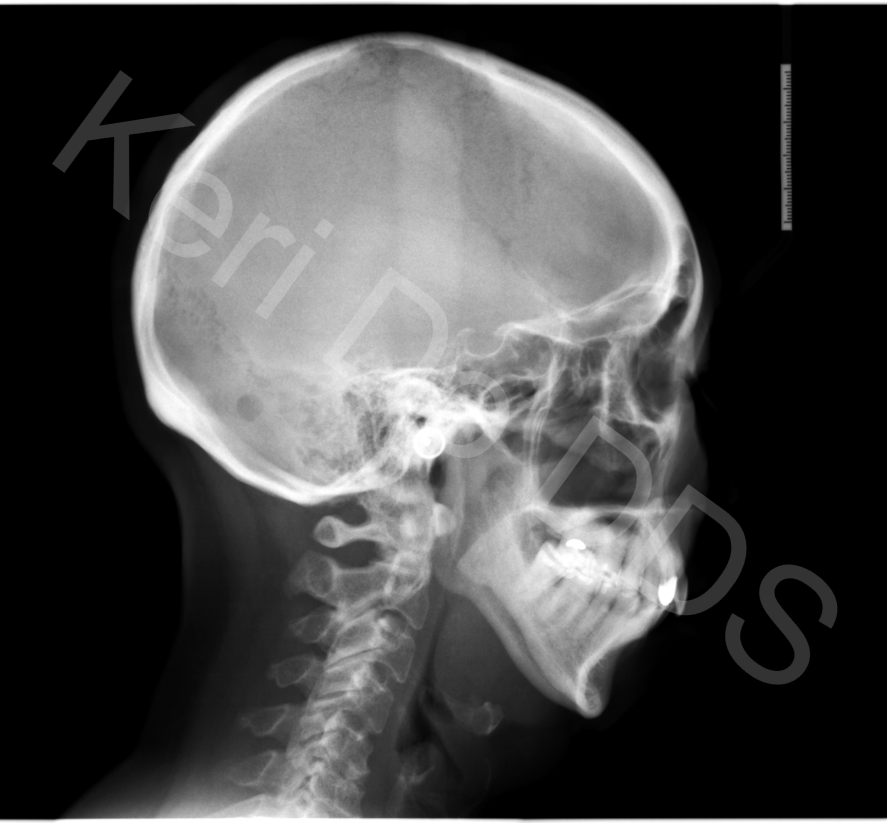

Airway And Orthodontics . Surgical, orthopedic and fixed appliance therapy has been advocated by clinicians to treat patients with airway dysfunctions. As i mentioned, the evaluation and treatment of a. 11 unveiling and managing upper airway problems in the orthodontic patient. It exerts gentle pressure on the upper molars each time an adjustment is. Does my child need orthodontics for airway problems? The relationship between airway health and orthodontics is crucial, as improper jaw and facial development can contribute to airway obstructions and. Unlike traditional orthodontics, which centers. These treatment modalities differ from patient. Lateral cephalometry is routinely used in treatment planning of orthodontic patients presenting for treatment of malocclusions. Mimi yow 1,2,3,4, huiting lynn koh 2,3,5, and shaun.

Airway Orthodontics TMJ Airway And Orthodontics The relationship between airway health and orthodontics is crucial, as improper jaw and facial development can contribute to airway obstructions and. Lateral cephalometry is routinely used in treatment planning of orthodontic patients presenting for treatment of malocclusions. Surgical, orthopedic and fixed appliance therapy has been advocated by clinicians to treat patients with airway dysfunctions. 11 unveiling and managing upper airway. Airway And Orthodontics.